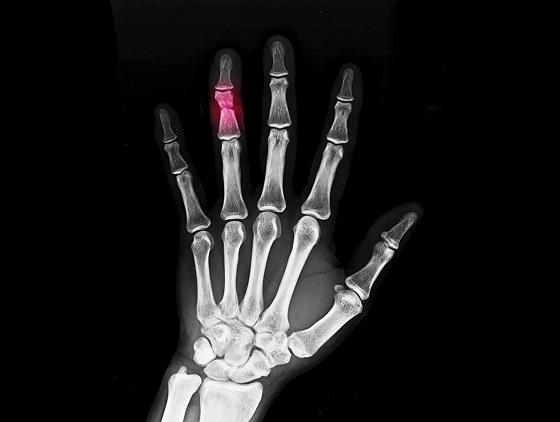

Cum se diagnosticheaza fractura de falanga

Diagnosticarea fracturii de falanga porneste de la anamneza pacientului, in care medicul se intereseaza despre cum s-a produs accidentul, unde doare, daca degetul a trosnit sau s-a deformat si daca poate fi miscat. Apoi urmeaza examenul clinic, in care medicul verifica alinierea, rotatia, sensibilitatea, circulatia si mobilitatea. Confirmarea fracturii se face prin radiografii, pentru a vedea exact unde este fractura de falanga si daca fragmentele sunt deplasate.